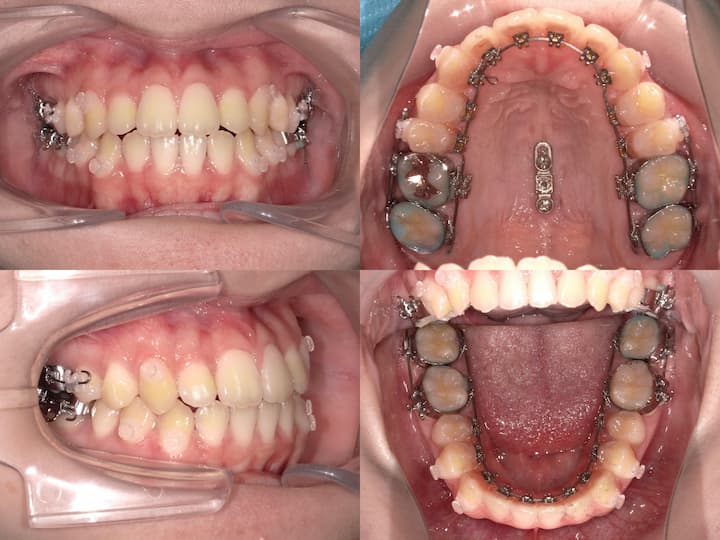

ハーフリンガル矯正装置を採用し、上顎は舌側矯正装置(リンガルブラケット)、下顎は唇側矯正装置(ラビアルブラケット)を使用しました。上顎大臼歯の圧下とアンカレッジコントロール

本症例の治療成功の鍵は、上顎大臼歯の確実な圧下とAngleⅠ級臼歯関係の維持にあります。以下の治療メカニクスを採用しました。

・i-station(歯科矯正用アンカースクリュー)の植立:正中口蓋縫合部に植立し、上顎大臼歯の固定源として使用

・上顎大臼歯の圧下:i-stationからの圧下力により、上顎大臼歯を垂直的に圧下

・上顎大臼歯の固定:抜歯スペース閉鎖時の近心移動を防止し、AngleⅠ級臼歯関係を維持

上顎大臼歯の圧下に際し、適切な咬合平面を維持するため、以下の対策を講じました。・フルサイズワイヤーの使用:.018×.025インチTMA(チタンモリブデン合金)ワイヤーを使用し、臼歯部のみが選択的に圧下するように設計

・パラタルバーの装着:上顎大臼歯の幅径を維持し、歯列弓形態の安定を確保

・前歯部の垂直的位置の維持:大臼歯圧下時に前歯部が挺出しないよう、ワイヤーで適切にコントロール